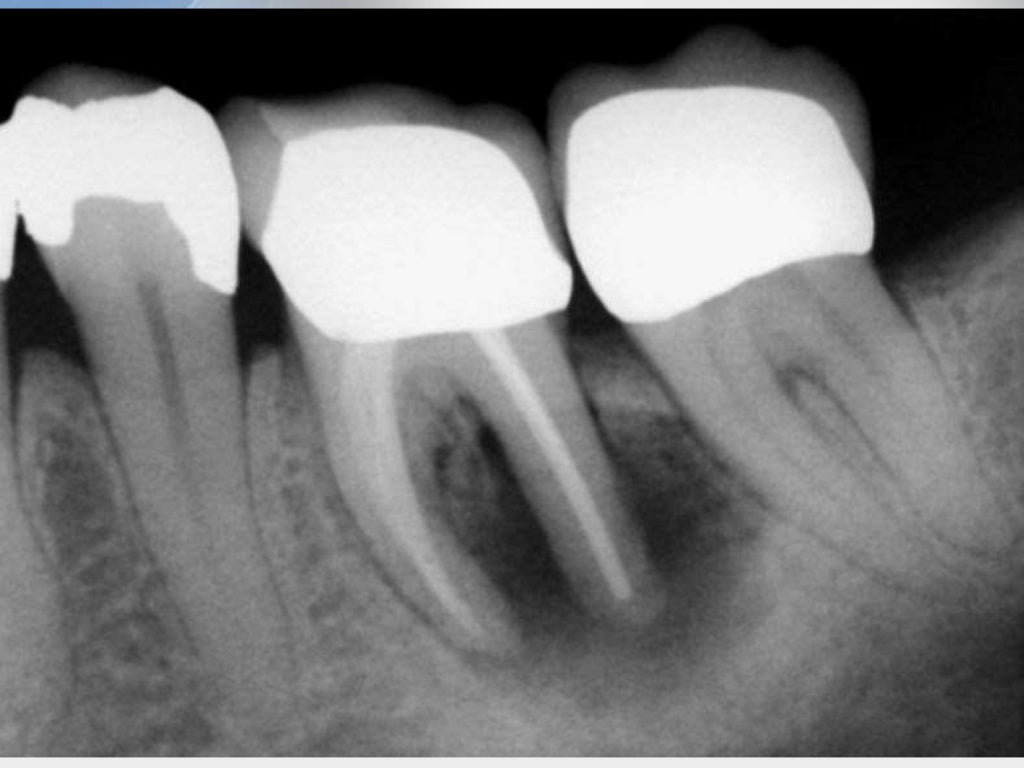

Microleakage Apical Seal vs Coronal Seal Semantic Scholar What Is Coronal Seal — the provision of a restoration with a good coronal seal has been suggested to reduce the risk of failure of a root canal. this paper will discuss aspects of: — coronal leakage is a phenomenon where debris and bacteria have found a way to seep from the patient’s oral cavity, past an. coronal sealing ability. What Is Coronal Seal.

(PDF) Microleakage Apical Seal vs Coronal Seal What Is Coronal Seal The use of leakage studies to assess the quality of. this paper will discuss aspects of: — the reasons for the improvement in endodontic success by placement of proper coronal restoration are firstly the coronal seal that prevents. coronal sealing ability is not the only factor that influences the seal of the canal and prevents apical leakage.. What Is Coronal Seal.